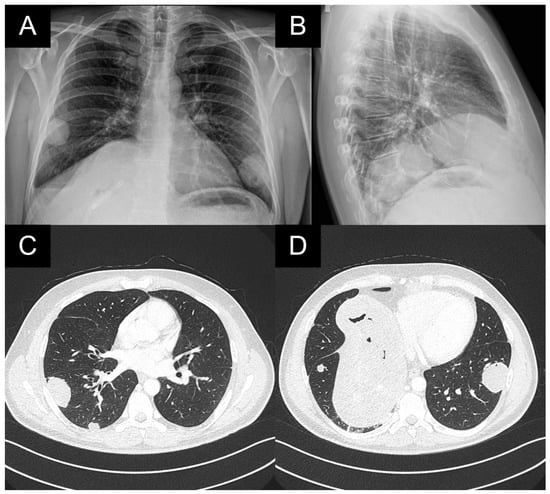

A patient with multiple bilateral lung lesions was diagnosed after investigations for a large hepatic lesion that turned out to be echinococcosis. A 41-year-old male patient reported abdominal pain and shortness of breath and was referred to the hospital by a primary care physician. Primary radiological investigations revealed a large hepatic lesion and multiple bilateral pulmonary lesions. Magnetic resonance imaging (MRI) was performed to evaluate the hepatic lesion (Figure 1), while chest X-rays and computed tomography (CT) were performed prior to admission to the Department of Thoracic Surgery. CT detected two right lower lobe lesions in segment 6 (diameters 4.6 cm, 1.4 cm) and one in segment 8 measuring 1 cm. In the left lower lobe, there was a single 4 cm lesion in segment 9 (Figure 2).

Figure 2. (A,B): Preoperative X-ray images of bilateral lesions in the lower lobes; (C): CT scan with the lesions in the right segments 6 and 8 measuring 4.6 and 1.4 cm; (D): 1 cm lesion in the 8th right segment and 4 cm lesion in the 9th left segment. An enlarged hepatic cyst percutaneously drained by hepatocentesis.